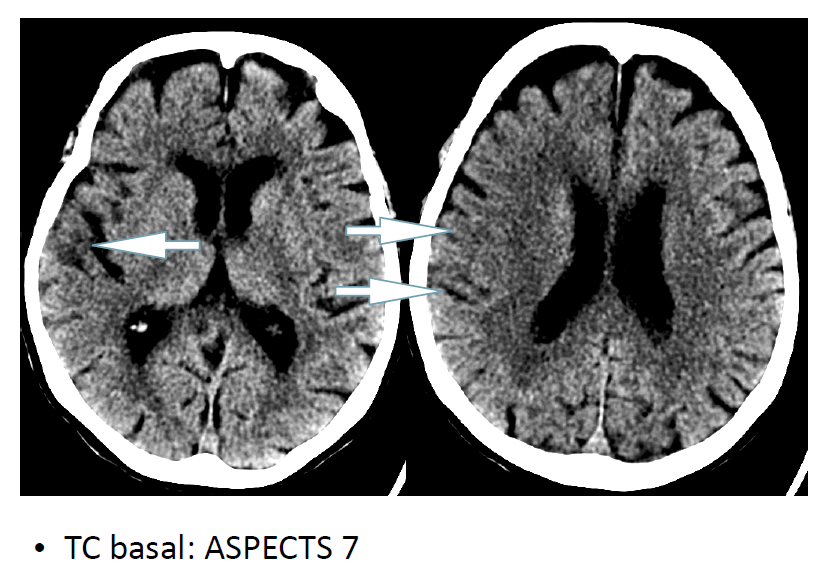

Complicación hemorrágica masiva tras trombectomía mecánica con aspiración en paciente añosa con antecedente neoplásico